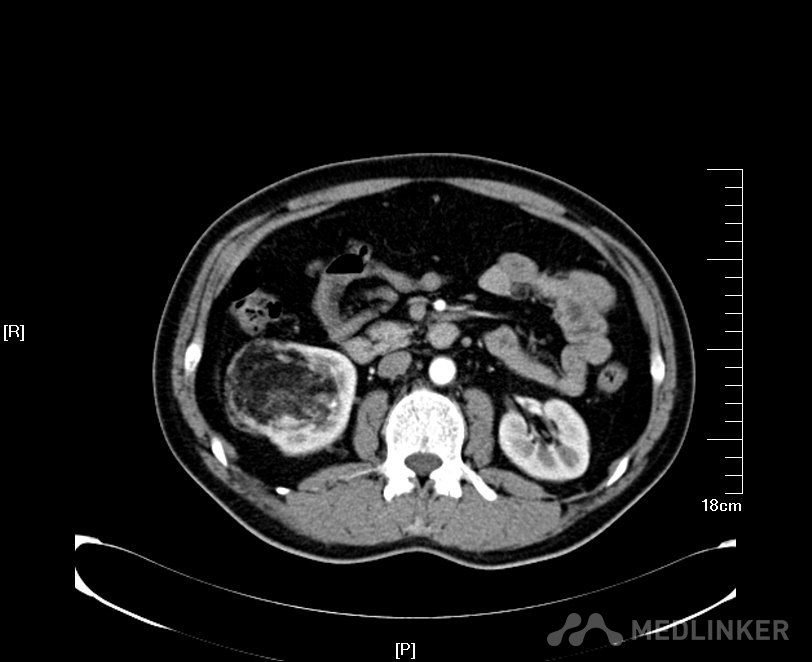

病例一 肾肿瘤患者(肿瘤大于4cm) 2016年02月手术患者,女,28岁,宜兴人,体检发现右肾占位5年,伴加重4月入院,患者5年前发现右肾错构瘤约2.0cm左右,每年于基层医院复查CT平扫检查,均未进行CT增强检查,肿瘤大小一直提示2.0cm左右,4月前单位体检B超发现右肾占位6.0cm左右,遂来我院复查彩色B超提示右肾上极高回声5.8*2.0cm,CT增强检查提示右肾肿瘤呈分叶状生长,突出肾脏表面约2.0cm左右,不排除肾癌可能;遂住院进一步治疗。术前GFR:左侧44.2ml/min,右侧51.3ml/min。术前诊断:右肾肿瘤;经讨论认为患者既往有右肾错构瘤良性肿瘤病史,近期肿瘤增大且呈现恶变倾向,考虑患者较为年轻,虽然肿瘤远大于4.0cm,为尽力争取保护其右肾,决定行腹腔镜下保留肾单位的右肾部分切除术。 我院彩色B超根据肿瘤血流情况判断肿瘤远非2.0cm,而是5.8*2.0cm左右

根据术前影像学检查术中精准定位右肾上极肿瘤